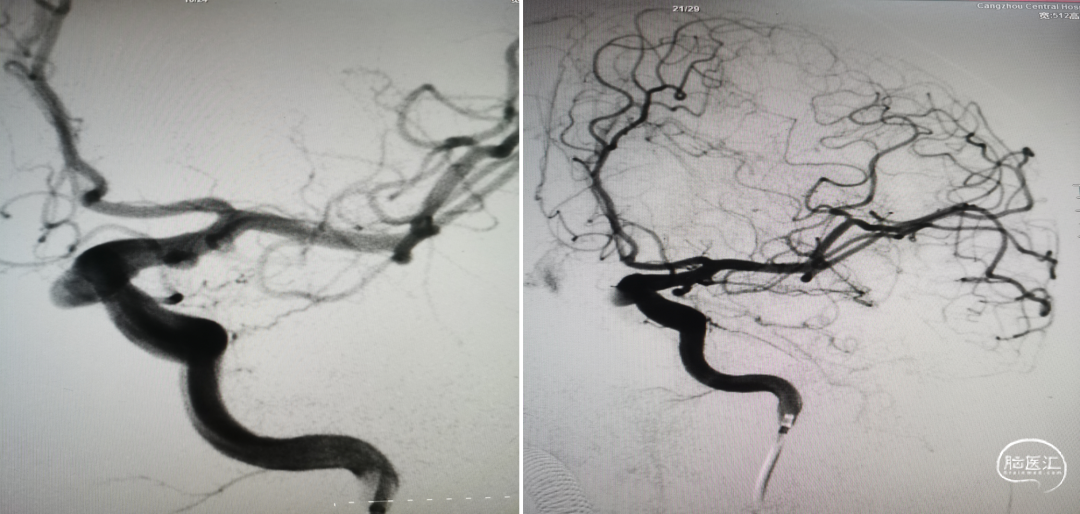

术后复查右颈内动脉造影(2022-12-27)

术后复查右颈内动脉3D重建

复查左颈内动脉造影(2022-12-27)

术后3D重建

术后3D图像及透视

术前、术后3D图像对比